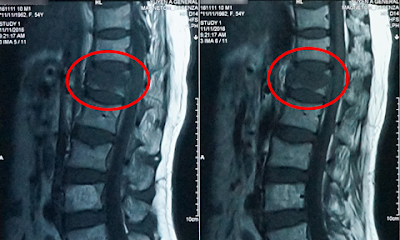

- MRI có thể cho thấy tủy sống, rễ thần kinh và những vùng quanh đó, cũng như nguy cơ xuất hiện của phì đại, thoái hóa và các khối u.

Xẹp đốt sống là hiện trạng thân đốt sống bị xẹp, dẫn tới biến dạng và giảm chiều cao thân đốt sống, gây đau nhức dữ dội. Trong đó, những vị trí xẹp đốt sống thường gặp nhất là đốt sống cổ, đốt sống ngực và đặc thù là xẹp đốt sống lưng do đây là vị trí phải chịu đa số trọng lượng của thân thể bên trên.